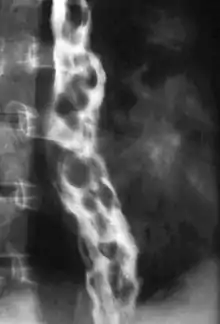

Esophageal varices are extremely dilated sub-mucosal veins in the lower third of the esophagus.[1] They are most often a consequence of portal hypertension,[2] commonly due to cirrhosis.[3] People with esophageal varices have a strong tendency to develop severe bleeding which left untreated can be fatal. Esophageal varices are typically diagnosed through an esophagogastroduodenoscopy.[4]

Dilated submucosal veins are the most prominent histologic feature of esophageal varices. The expansion of the submucosa leads to elevation of the mucosa above the surrounding tissue, which is apparent during endoscopy and is a key diagnostic feature. Evidence of recent variceal hemorrhage includes necrosis and ulceration of the mucosa. Evidence of past variceal hemorrhage includes inflammation and venous thrombosis.

Therapeutic endoscopy is considered the mainstay of urgent treatment. The two main therapeutic approaches are variceal ligation (banding) and sclerotherapy.